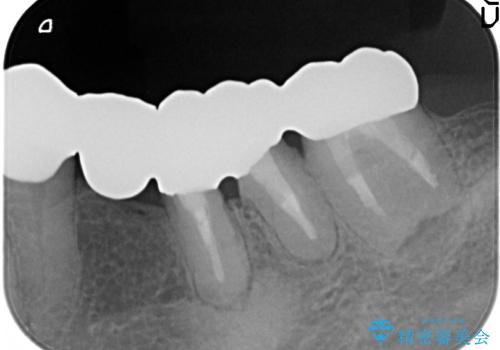

手術後に根管治療を行い、歯肉と骨の治癒を十分に待った後ブリッジによる補綴治療を行いました。

ご希望通り歯を抜かずに残すことができ、喜んで頂けました。

セルフメンテナンスしやすいよう、ブリッジと歯ぐきの間に歯間ブラシを通すことができるように作製しています。

咬合関係により奥歯の負担が大きいため、今後も注意深く経過観察していく予定です。

被せ物の種類:オールセラミッククラウン ベレッツァ